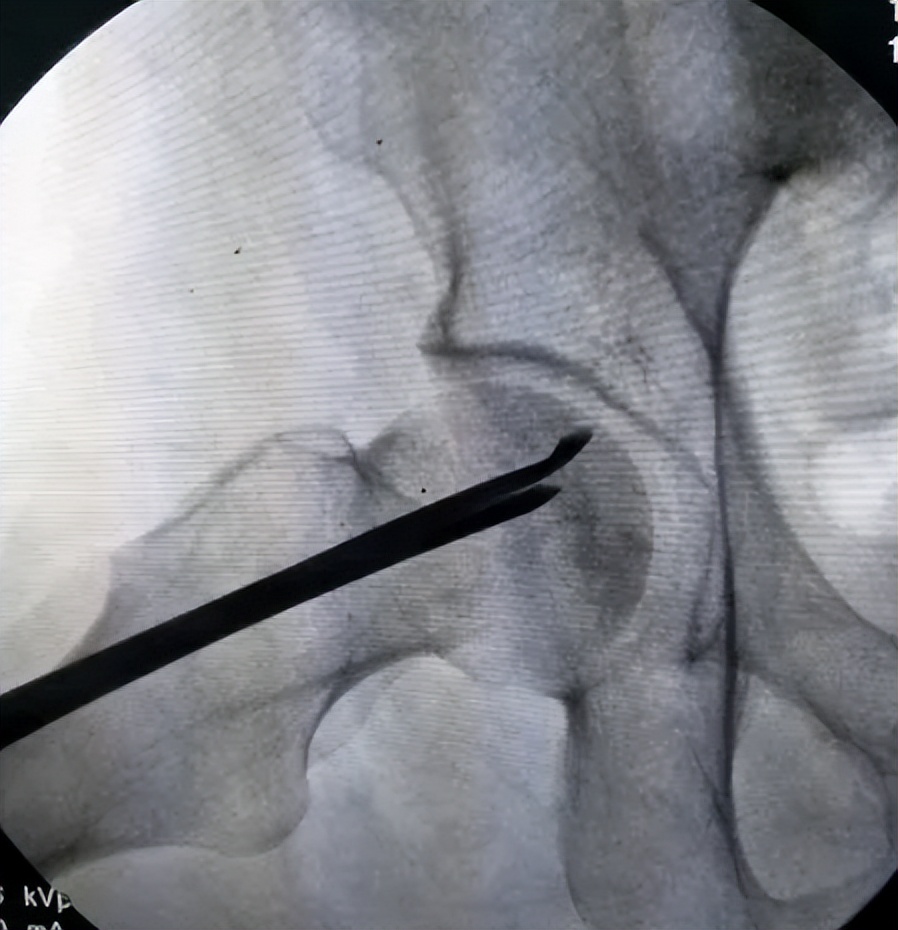

Aggarwal等前瞻性地研究了PRP联合髓芯减压术(Coredecompression,CD)与单纯CD治疗股骨头坏死的疗效,发现PRP联合CD治疗后疼痛评分、功能评分、HHS均有所改善;

同时延缓疾病进展,降低股骨头塌陷机率、提高全髋关节置换术的生存率,以上结果表明与单纯CD相比,术后使用PRP可明显缓解疼痛 ,改善中期功能预后,改善髋关节置换术和股骨头塌陷早期患者的手术存活率。

然而也有研究表明股骨头坏死保髋术后应用PRP可导致患者出现血液高凝状态,使血栓风险增高。